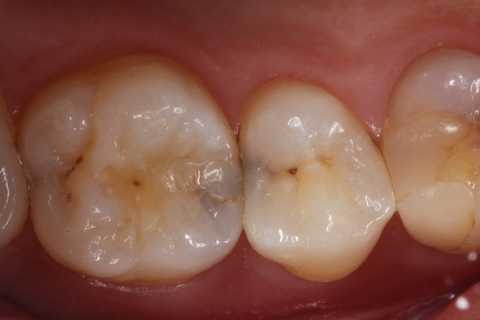

20代女性、右上6、咬合性外傷による隣接面カリエス

クラックが気になるのだが、象牙質には広がっていないようだったので、このまま充填した。

では時系列でどうぞ

実像から